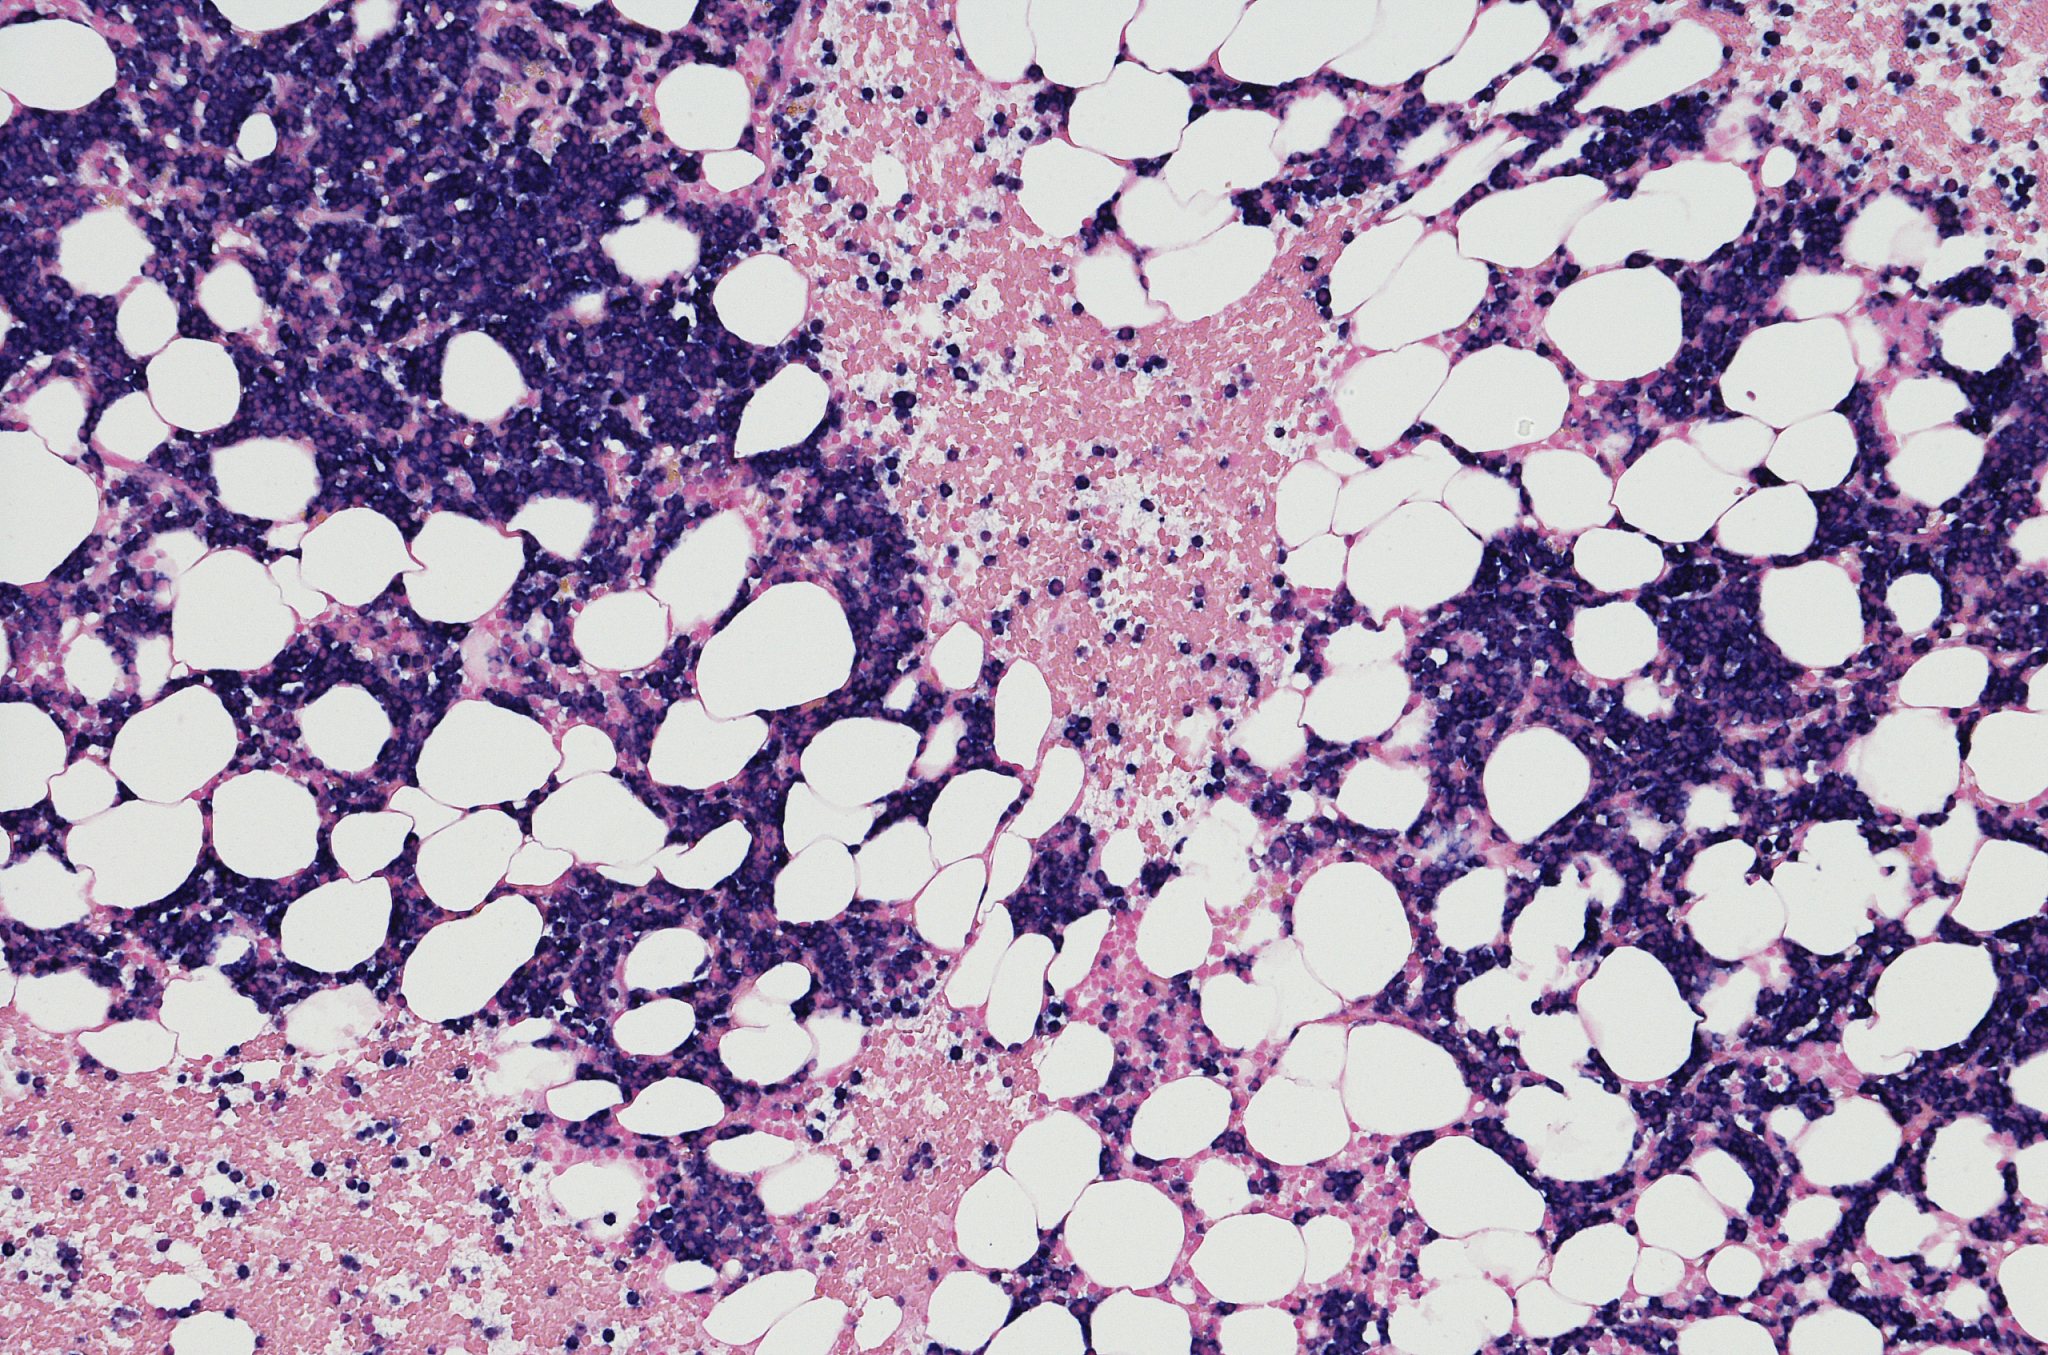

多发性骨髓瘤是一种由恶性浆细胞在骨髓中增生引起的癌症,其 Kappa/Lambda 比值通常高于 1.5。淋巴瘤影响淋巴系统中的淋巴细胞,某些患者的 Kappa/Lambda 比值也可能升高。